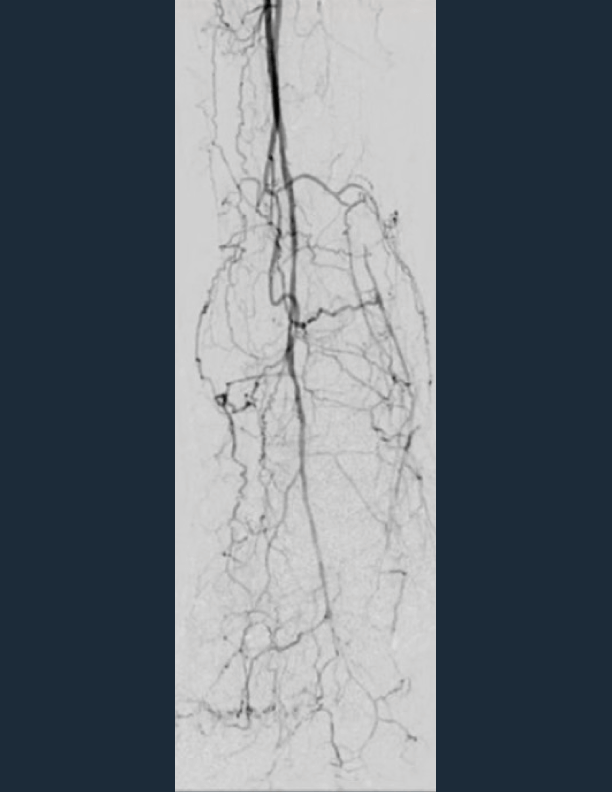

• AP view shows no plantar arch or flow to metatarsals arteries and no pedal pulse present

AP view shows no plantar arch or flow to metatarsal arteries and no pedal pulse present.